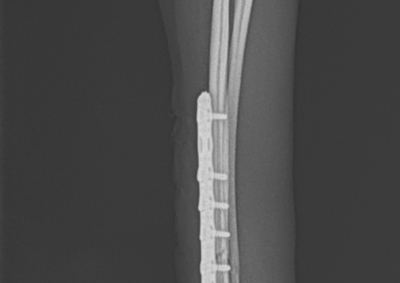

注意 ボタンをクリックした先に、治療中および手術中の画像が説明で使用されている場合がございます。 そのような画像に弱い方は閲覧なさらないようお願いいたします。 整形外科 若齢犬の橈骨固定術 #271 整形外科 前十字靭帯断裂(中型犬)に対するCBLO #255 整形外科 超小型犬に対する上腕骨遠位Y字骨折 整形外科 大型犬の前十字靭帯疾患(慢性経過)に対するCBLO #254 整形外科 橈骨固定術 #270 整形外科 膝蓋骨内方脱臼に対する人工滑車置換術 PGR #23 整形外科 犬の前十字靭帯(疾患)部分断裂に対するCBLO #253 整形外科 犬の前十字靭帯断裂に対するCBLO #252 整形外科 膝蓋骨内方脱臼+前十字靭帯断裂に対するPGR#22・LSS 整形外科 大腿骨骨折 整形外科 橈骨固定術 #269 整形外科 上腕骨外顆骨折の癒合不全 123456> 症例カテゴリー 放射線治療整形外科軟部組織外科脳神経外科内科腫瘍外科救急・集中治療リハビリテーション科腫瘍内科内視鏡科脳神経科呼吸器外科中医・漢方猫の腎移植循環器科